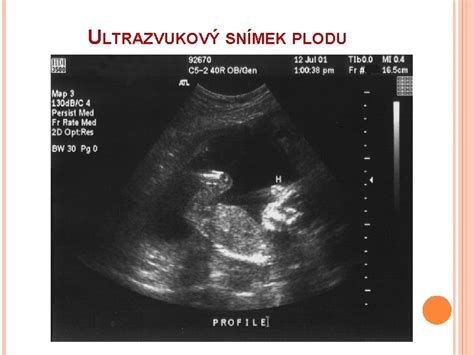

Vývoj pohlavia: Hoci je o pohlaví rozhodnuté už pri oplodnení v 3. týždni, budúce mamičky sa ho najčastejšie dozvedajú okolo 20. týždňa tehotenstva prostredníctvom ultrazvukového vyšetrenia, ak sa bábätko vhodne natočí.